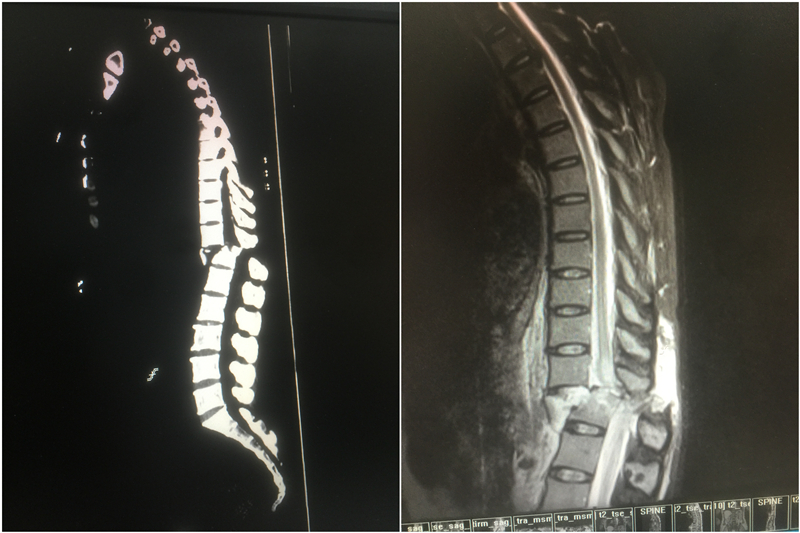

經(jīng)過在急診科緊張的搶救,以及一系列快速檢查后,檢查結(jié)果顯示,傷者周女士胸12椎體爆裂骨折,胸12椎體對應(yīng)的脊髓橫斷傷,胸11椎體Ⅳ度脫位。

胸12椎體爆裂骨折

胸12椎體對應(yīng)的脊髓橫斷傷

胸11椎體Ⅳ度脫位